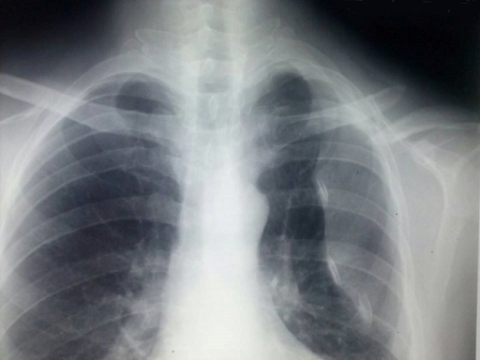

Pada foto ro thorax di atas, tampak ada gambaran fraktur klavikula sinistra serta gambaran pneumothorax yang kemungkinan terjadi akibat fraktur tersebut.

Untuk penanganan pneumothorax bisa dengan pemasangan ICC. Sedangkan untuk penanganan fraktur klavikula, bila ada pergeseran >2cm, maka bisa dipertimbangkan untuk terapi secara operatif.

kalau saya setuju dengan pendapat dr. Georgiana dimana hasil dari foto tersebut menunjukkan adanya gambaran fraktur klavikula dan pneumothoraks. Mungkin penanganannya bisa juga dilakukan secara konservatif kecuali ada luka terbuka baru bisa dipertimbangan secara operatif.

Saya pernah menemukan kasus serupa. Pada pasien ini pertama dapat dilihat dulu pada pemeriksaan fisik apakah ada suara napas yang hilang pada salah satu atau kedua sisi paru. Kemudian dapat juga dilakukan perkusi pada dinding dada, jika terdapat hipersonor dan didukung dengan gambaran radiologis seperti di atas maka mungkin terjadi suatu pneumothorax.